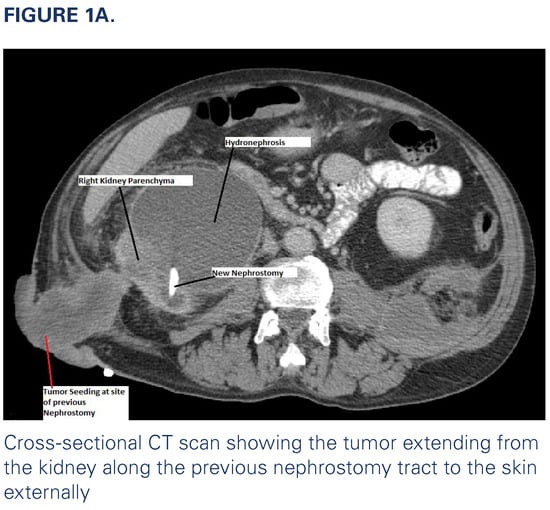

A 57-year-old man, with a history of nephrolithiasis and heavy smoking (80 pack years at presentation), presented to a tertiary cancer center 2 years ago with urothelial carcinoma (UC) in the right distal ureter associated with lung metastasis. On initial presentation, the patient complained of right flank pain, gross hematuria, and weight loss. Imaging revealed a 3.7 cm right distal ureter mass with severe right hydronephrosis (Figure 1a) and a 3.2 cm lung lesion, which was proven by biopsy to be metastatic UC. A right nephrostomy was inserted for palliation of symptoms and to manage recurrent obstructive pyelonephritis. The patient’s disease progressed despite multiple lines of chemotherapy and immunotherapy. He developed infection at the nephrostomy site with associated emphysematous pyelonephritis. This was managed with antibiotics and placement of a new nephrostomy at a different site, and palliative nephrectomy was considered. After resolution of the infection, the patient was noted to have a small malodorous mass at the site of the previous nephrostomy that progressively grew in size over 4 months (Figure 1b). Biopsy of the mass revealed UC.